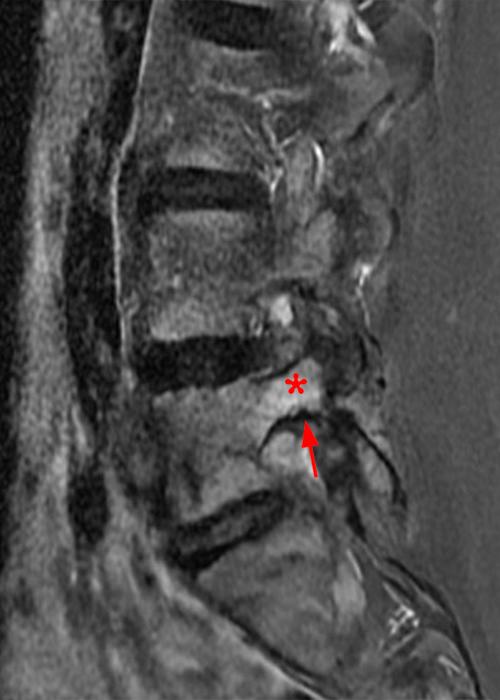

Case 1: 14-year-old female with back pain after a car accident. Axial T2-weighted (1A) and sagittal STIR (1B) images are provided. What are the findings? What is your diagnosis?

Case 1: T2-weighted axial (3A) and sagittal STIR (3B) sequences show marked cortical T2/STIR hyperintensity in the left pedicle of L5 surrounding a hypointense line (arrows) which begins at the inferior/medial margin of the pedicle and nearly completely traverses the pedicle.

Case 1: Acute left-sided pediculolysis